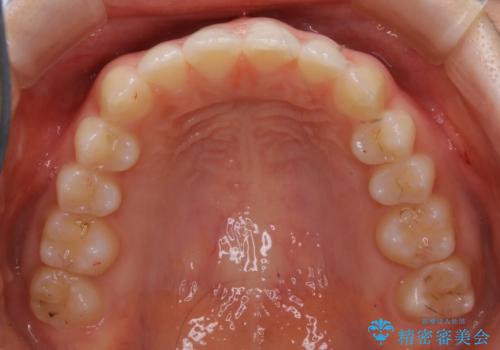

- 上下前歯のがたつきが気になるとご相談にいらした方です。

一見前歯のがたつきだけ改善させれば良い様に見えますが、このがたつきの原因は奥歯の嚙み合わせのズレからくるものであったため、インビザラインFULLで噛み合わせの改善から行っていきました。前歯の角度も改善されたために頑張って唇を閉じる必要がなくなり、横顔のシルエットも綺麗になりました。

前歯のがたつきだけを治そうとした場合、噛み合わせは二の次なってしまう事が多く、せっかく綺麗になった歯並びも後戻りしやすくなります。奥歯の噛み合わせからしっかり機能させることで、長期間にわたって綺麗な歯並びを保ちやすくなります。